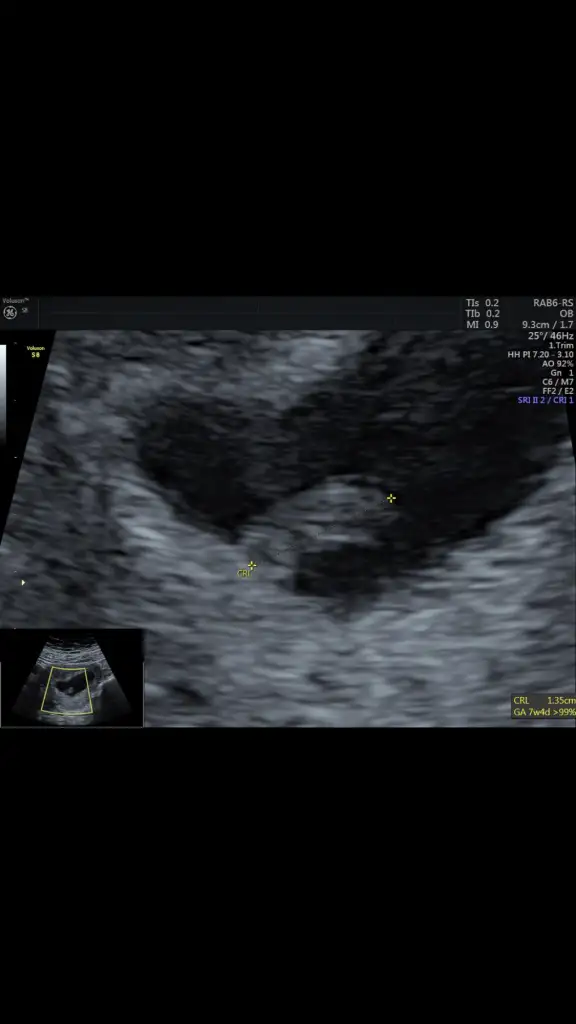

Bence bu hepsini yalanlıyor 6 haftalık kız 7 haftalık erkek gibi duruyor. Demekki bebeğin yeri surekli değişiyor teori yalan

Zaten erken usgye bakılıyor bebeğin yeri değişmeden önceki haline yani. O yüzden 6 haftalık olanı daha çok önemsiyorlar 7 haftalık olanda ortaya gelmiş artık bebek. Yinede çok bilimsel değil bu teori bende teoriye bakınca kız düşündüm. 7 haftalık da ortada olduğu için mi erkek dediniz merak ettimBence bu hepsini yalanlıyor 6 haftalık kız 7 haftalık erkek gibi duruyor. Demekki bebeğin yeri surekli değişiyor teori yalan

6 haftalık sağ tarafta 7 haftalık sola yakın. Ben 5 haftalıkken kanama şikayeti ile dr a gittim .dr bebek yerleşmeye çalışıyor kesenin içinde sürekli yer değiştiriyor uygun yer bulana kadar oyüzden kanama olabilir dedi.Zaten erken usgye bakılıyor bebeğin yeri değişmeden önceki haline yani. O yüzden 6 haftalık olanı daha çok önemsiyorlar 7 haftalık olanda ortaya gelmiş artık bebek. Yinede çok bilimsel değil bu teori bende teoriye bakınca kız düşündüm. 7 haftalık da ortada olduğu için mi erkek dediniz merak ettim